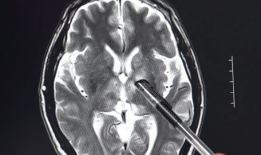

脑膜刺激征检查视频,直观解析临床诊断技巧

你有没有想过,去医院看病的时候,医生有时候会给你来点“特殊待遇”?比如说,给你做个脑膜刺激征检查。这听起来是不是有点陌生?别急,...